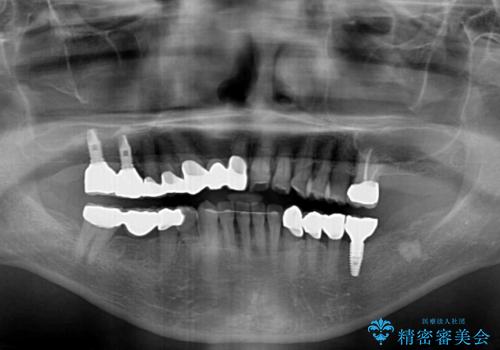

数多くの外科処置を行ったため、治療期間は長期間となりました。

一方、外科処置をしっかりと行ったことで、歯周病の状態は改善され、安定した状態にしあげることができました。